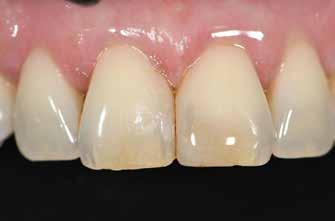

Nem volt kedvencem, de kevésbé kedveltem a hibrid technikát, ahol a palatális fal wax-uppal történő felépítése, majd a nyaki terület szabadkézi megerősítése után a restauráció többi részét mátrixszal lehetett kivitelezni (1. ábra). Bár a kezemben ez valahogy hatékony volt, mégis bonyolult volt.

1. ábra: A wax-up alapú technikák gyakori problémái, a szájpadlásfal apikális része hibás.

2-4. ábra: Gyakori problémák klasszikus megközelítéssel. 5. ábra: Tökéletes vészhelyzeti profil elülső szárnyas technikával. Dr. Jun Iwata, Japán jóvoltából.